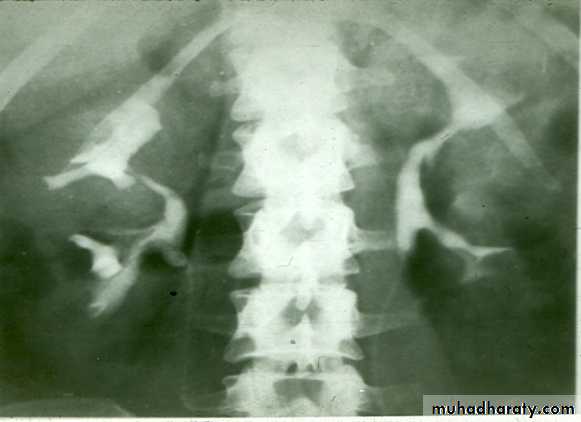

Fusion of lower pole of both kidneys by bridge of renal tissue (isthmus) crossing in front of aorta, spine and IVC.

IVU shows :

The kidneys at low position .

Close to the spine with long axis parallel to the spine .

Mal–rotation manifested by medially directed calyces.

The renal pelvis and ureters are anterior and lateral in position .

Fusion of upper poles is rare.

HORSE –SHOE KIDNEY

HORSE SHOE KIDNEY